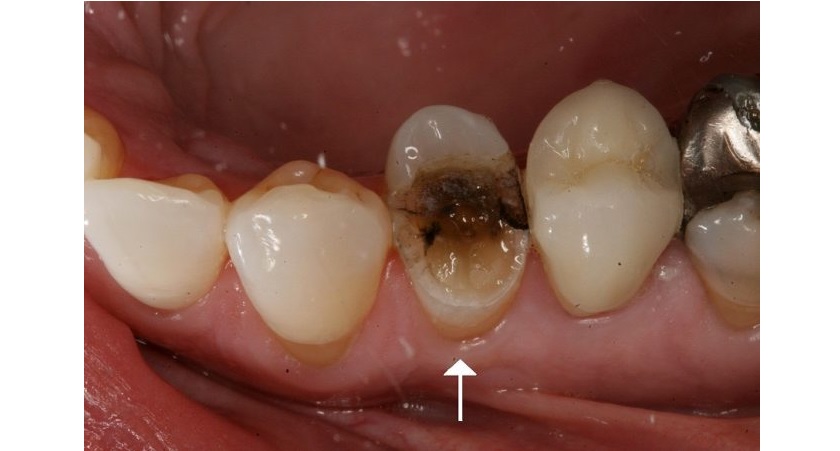

Trên thực tế, có rất nhiều nguyên nhân khiến tủy bị tổn thương và chết. Và nguyên nhân cơ bản thường gặp nhất đó là sâu răng, nứt vỡ răng hay mắc các bệnh lý răng miệng khác như viêm quanh răng… Khi tủy chết không điều trị kịp thời thì vùng viêm sẽ lan xuống chóp chân răng, gây tiêu xương xung quanh, xuất hiện lỗ rò sưng lợi và phá hủy xương hàm.

Các trường hợp được chỉ định lấy tủy răng bao gồm sâu răng nặng vào tủy, răng bị chấn thương dẫn đến sứt mẻ, tủy răng chết gây đau nhức lan vào xương. Tủy răng ban đầu được bảo vệ bởi men răng và ngà răng, nhưng với những tổn thương nghiêm trọng thì sẽ gây ảnh hưởng đến tủy răng và phải lấy tủy răng.